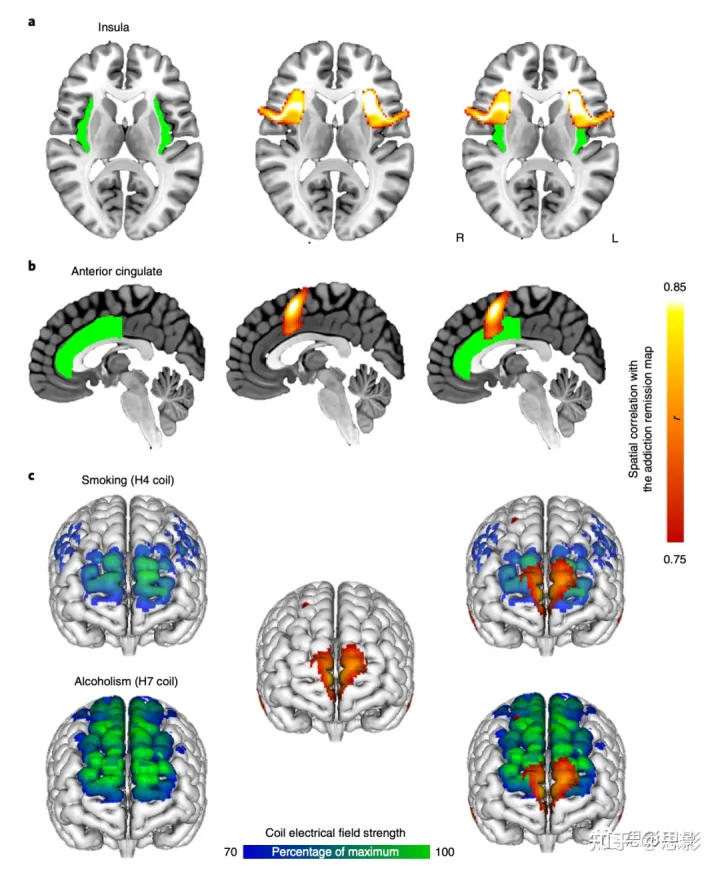

最后,我们研究了哪些脑体素的连接特征与破坏成瘾的病变位置的连接特征最匹配。理论上,该图中的正节点表示放置局灶性病变以破坏成瘾的理想位置,而该图中的负节点表示兴奋性脑刺激的理想位置,例如高频 TMS。峰值正性节点位于左侧额叶皮层,与先前的病变研究突出显示的左岛叶相邻,并且位于扣带回,正好在先前用作成瘾手术损伤靶点的扣带回上方(图 4)。峰值负节点位于内侧额极皮层,与 FDA 最近批准用于戒烟的 TMS 线圈的最大电场重叠,并且 TMS 线圈在概念验证研究中显示出治疗酒精依赖的功效(图 4)。

图4:完善成瘾的神经解剖学治疗靶点。

a-c,基于先前工作治疗成瘾的神经解剖学靶点包括岛叶(绿色,a),前扣带(绿色,b)和额叶皮层(H4和H7 TMS线圈的电场模型以蓝绿色显示,c)。体素的连通性特征最符合我们基于病变的成瘾缓解网络,包括左眼睑/岛叶(红黄色,a),扣带旁回(红黄色,b)和内侧额极皮层(红黄色,c)。使用LNM确定的治疗靶点与先前的靶点(右图a-c)重叠,但也为如何完善或改进这些靶点提供了可测试的假设。 补充图12显示了H4和H7 TMS线圈(c)的电场模型的其他图像。